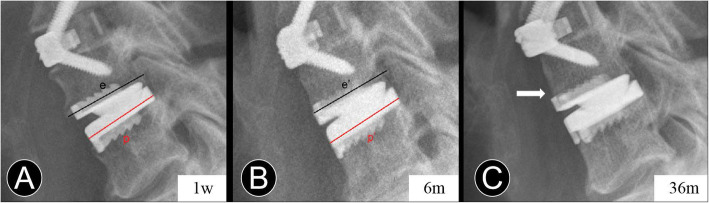

Fig. 2.

Measurement of anterior bone loss. a and b Immediate and 6-month postoperative lateral radiographs, p and p’ are the length of the prostheses. e and e’ are the length of the endplates. EL% = 100% × (e / p) / (e’ / p’). c At the last follow-up, the lateral radiograph shows peri-prosthesis bone loss at the anterior vertebral body margin (white arrow)